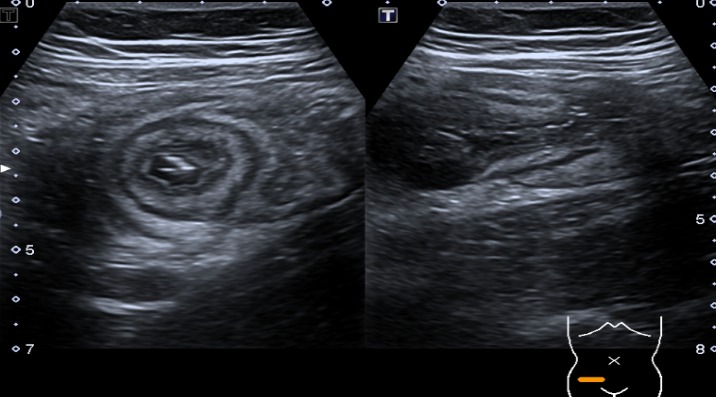

Esclerosis tuberosa: diagnóstico prenatal, tratamiento y seguimiento de un año. Reporte de caso

Yolima Alfaro, Luis Fernando Molineros, Gabriel Del Castillo, Melissa Charria Caicedo, David Farah Borrero